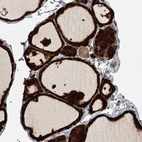

Immunohistochemical staining of human thyroid gland shows strong cytoplasmic positivity in glandular cells.